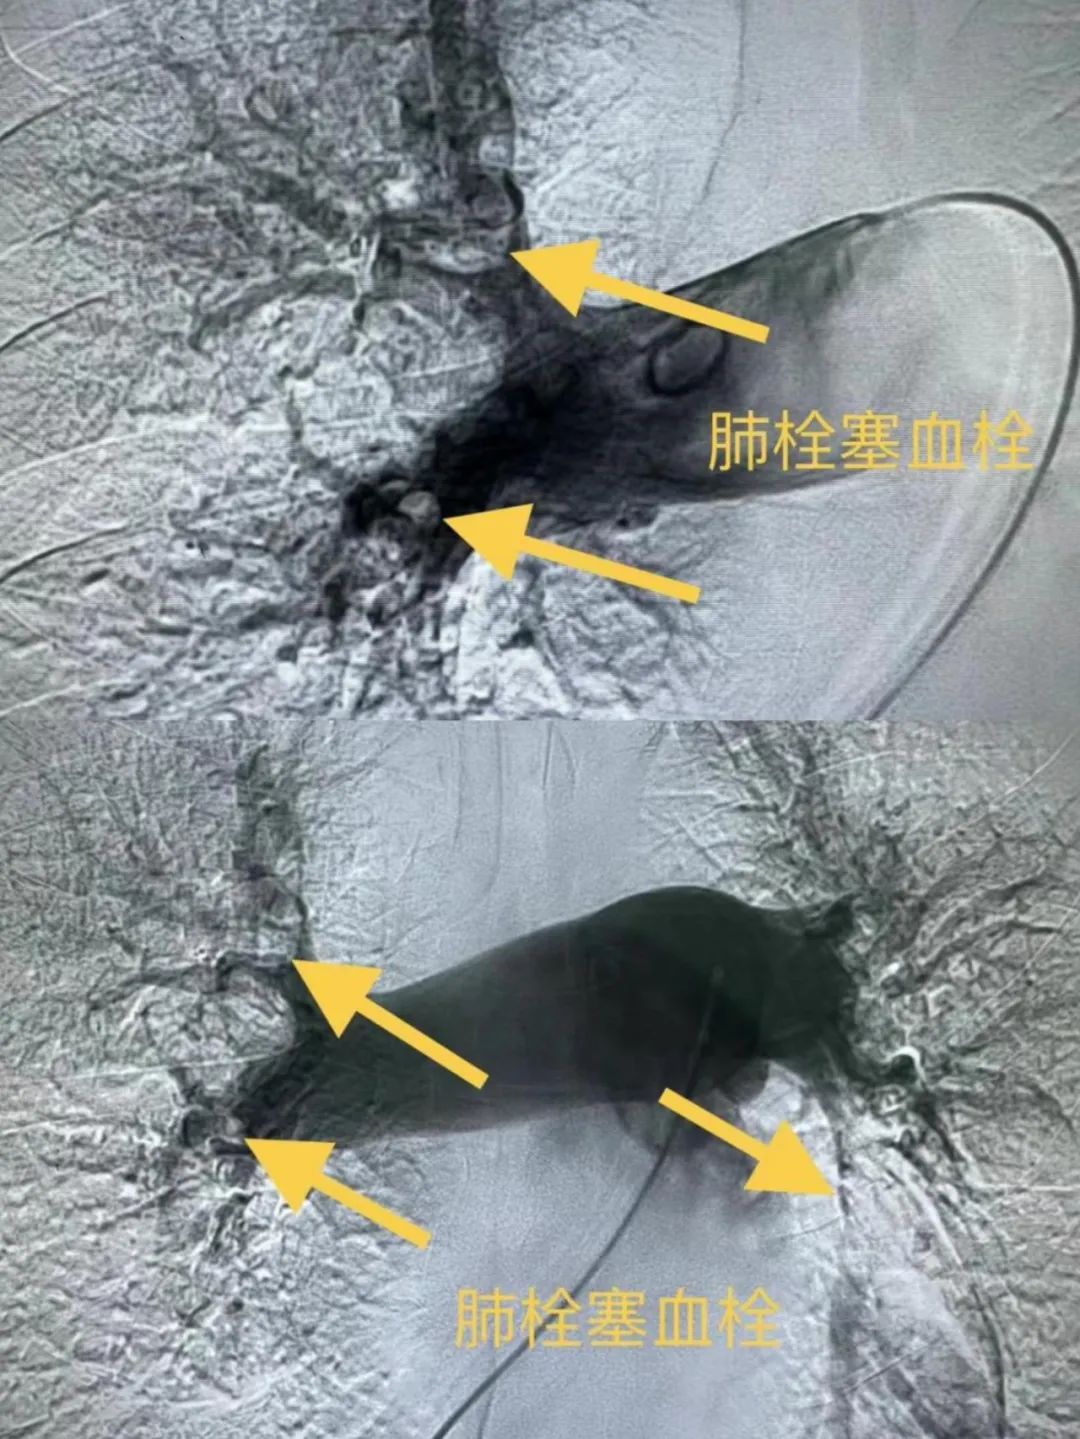

患者金某,女,61岁。主因“突发心悸伴晕厥3小时”,查体见左下肢肿胀,SaO295%,心电图提示“SIQIIITIII,不完全性右束支传导阻滞,ST段下移”;肌钙蛋白I0.248ng/ml,血浆D-二聚体5703ng/ml,考虑急性肺动脉栓塞或急性冠脉综合征;因患者存在过敏史,无法完成肺动脉联合冠状动脉CTA检查,胸痛中心与血管肿瘤介入科VTE项目联合会诊,拟行心肺联合造影检查及介入治疗,结果提示左冠前降支轻度狭窄,双侧肺动脉栓塞,给予肺动脉尿激酶溶栓、静脉滤器置入,术后患者病情平稳症状好转,手术由胸痛中心郑凯、巴根那联合血管肿瘤介入科梁羽、那日苏等几位医师共同完成。

患者李某,男,70岁。既往高血压病史3年。主因“头晕、气短3天”,查体见左下肢稍有肿胀,SaO291%;VTE绿色通道行CTPA提示大面积肺栓塞,血浆D-二聚12.12ng/ml;考虑急性肺动脉栓塞;立即为其行肺动脉造影、下腔静脉滤器置入、肺动脉溶栓药物灌注术进行治疗,术后SaO295%。手术由血管肿瘤介入科魏东升主任、梁羽、那日苏几位医生合力完成。以上2例患者经术后予抗凝溶栓治疗,均已康复出院。